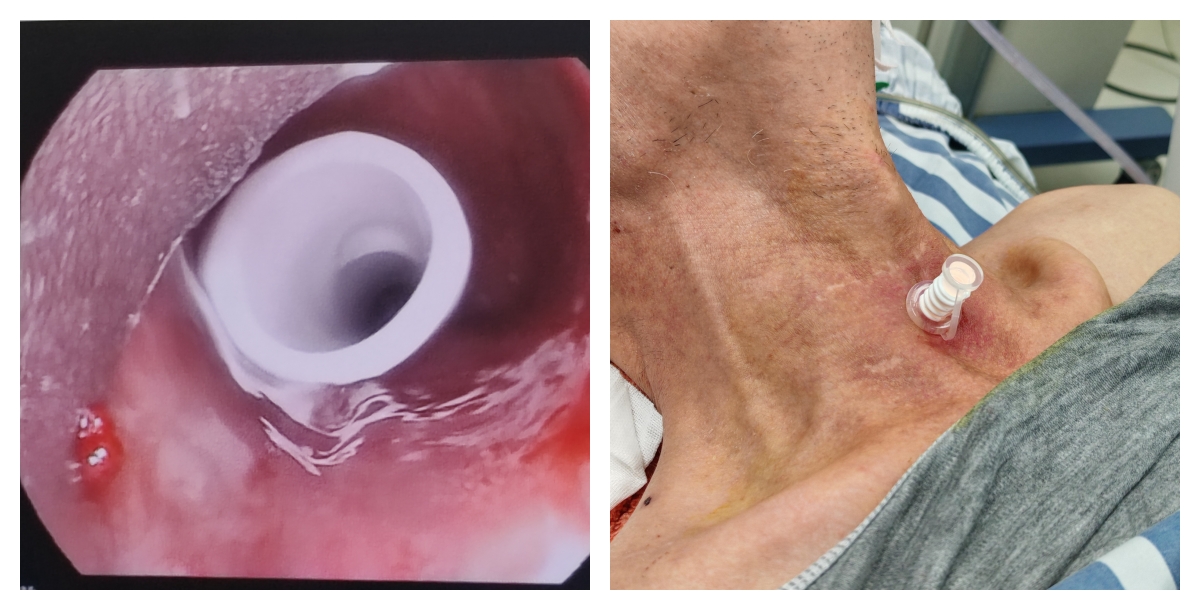

经与家属充分沟通并获得知情同意后,12月9日下午,呼吸介入团队联合麻醉手术科、耳鼻咽喉头颈外科组成多学科协作小组,经外院专家指导,在全麻下硬质支气管镜精准抵达声门下1cm处,随后依据镜下实测数据现场修剪安全T管,在血管钳辅助下将T管经气切瘘口精准置入,外支固定,一气呵成,整个手术过程顺利有序。

术后,患者气道即刻通畅,呼吸明显改善,吞咽功能也得到有效恢复。虽然因声门功能未完全恢复,暂时仍不能发声,但已无需再承受窒息与反复感染的折磨,生活质量得到显著提升。家属感慨万千:“原以为他这辈子都要在窒息和感染中度过,没想到一根‘T’形管,把他从鬼门关拉了回来,也让我们一家人重新看到了希望!”